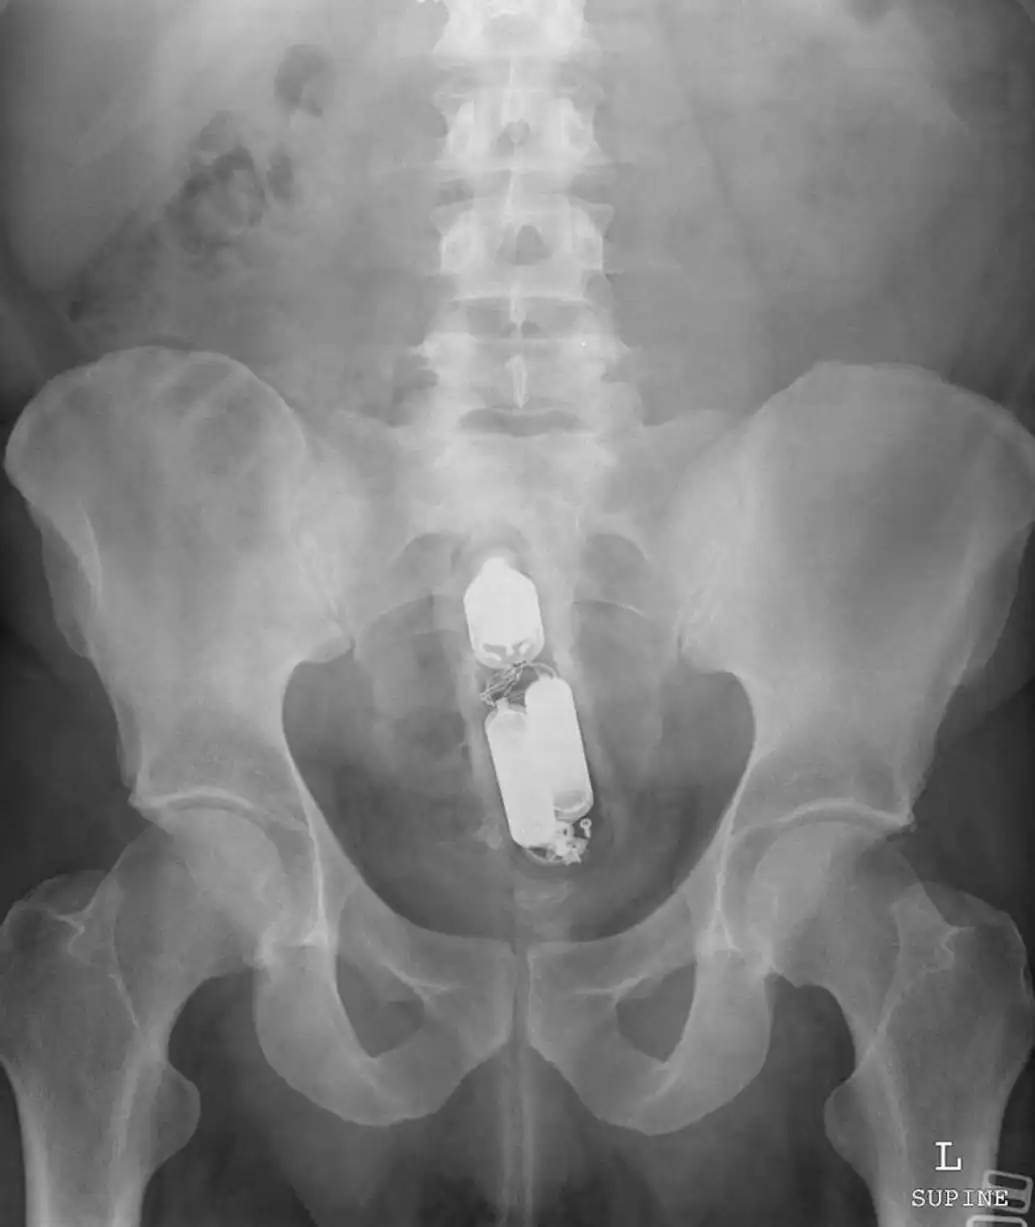

Врачебные находки в интимных местах

Или как впихнуть невпихуемое :lol: